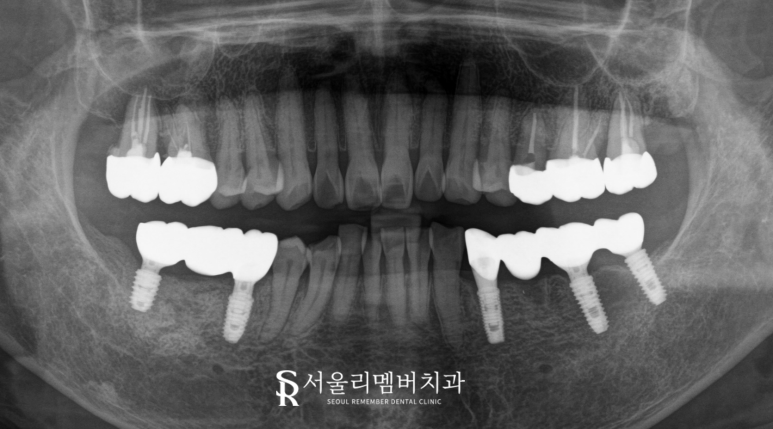

촬영일:2024.11.05

진료가 완료된 모습을

봉천동 치과 와 같이 확인하겠습니다.

스케일링을 통해

치석과 치태를 먼저 제거했습니다.

그 후 치근을 발거하고

임플란트와 브릿지를 통해

자연치를 대체했습니다.

더불어 치관이 마모되고

오래된 보철에 문제가 생겼던 곳도

자연치를 살려서

지르코니아로 덮어씌워

보호해 주었습니다.